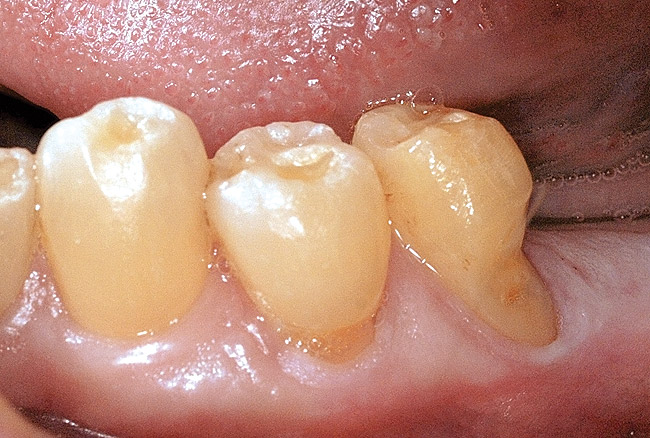

Figure  3  Severe dental erosion and attrition in a GERD patient.

Figure 3

Characteristics of damage to tooth structures caused by acidity include wear on the occlusal surfaces of molars and a saucer shape on the cusps of molars (perimolysis).12 The erosion can vary from minor and subtle changes on the tooth surface, ie, loss of luster, a dull or matted look, to cupping on occlusal surfaces or incisal edges, which may extend to dentin. Usually, the erosive lesions demonstrate greater width than depth. When combined with abrasive forces or stresses, the tooth surface loss may occur at a faster rate (Figure 2, Figure 3, Figure 4 and Figure 5).